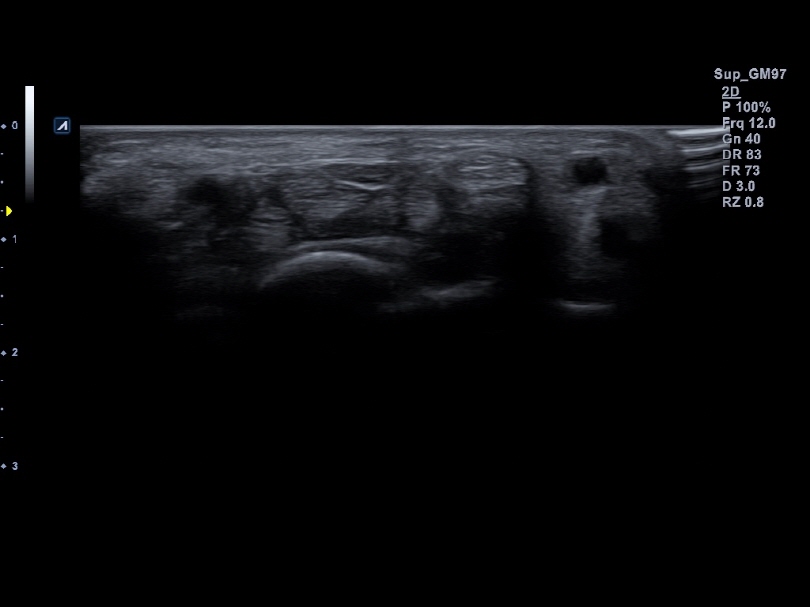

IO8-17T

High frequency hockey stick (8-17MHz)

Application:

Small Parts, MSK